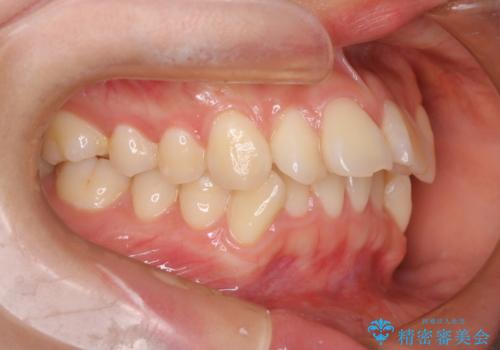

- 出っ歯、ガタツキ、噛み合わせが気になるとのことで来院された患者様です。

小臼歯を抜歯することでスペースを作り、前歯を下げて口元を下げ、Eラインを改善する治療方針としました。

表側のワイヤーは見た目が気になるとのことで、上の歯だけ裏側に付くハーフリンガルという装置で治療を行いました。